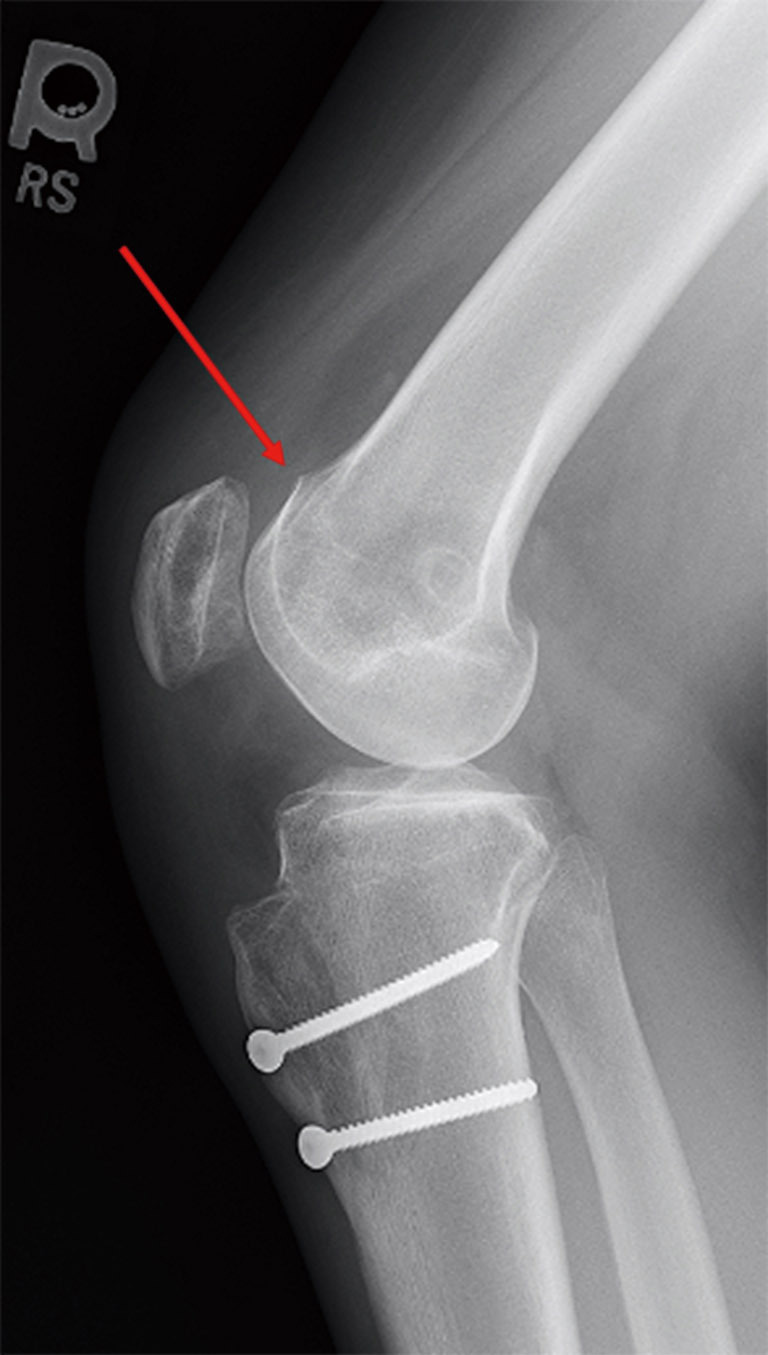

Patellar instability is a common clinical problem that primarily affects the adolescent and young adult population. The demographic and anatomic risk factors that predispose patients to patellar instability are multifactorial and include young age, female sex, trochlear dysplasia, elevated tibial tubercle to trochlear groove distance (TT-TG), patella alta, femoral and tibial malalignment, ligamentous laxity, and lack of neuromuscular control. There have been substantial efforts to predict which patients who sustain a first-time dislocation will go on to incur additional dislocations. This is particularly important because with each dislocation event, there is a significant risk of injury to the patellofemoral joint including both medial patellofemoral ligament (MPFL) stretch or rupture and damage to the cartilage which can range from simple fissures to full-thickness cartilage defects and osteochondral fractures. Prediction models have demonstrated that amongst first time dislocators, young patients with trochlear dysplasia are at the highest risk for redislocation. The current standard of care for treatment of first-time dislocators without a loose body or osteochondral fracture is nonoperative management. However, recently there has been a focus on implementing a risk-stratified approach to the surgical indications for a first-time dislocator as the high-risk population might be better treated with early surgical stabilization to prevent or reduce their risk of recurrent dislocation and its associated morbidity. Likewise, for patients with recurrent dislocations, it remains to be determined whether an isolated MPFL reconstruction is sufficient for high-risk patients with several poor prognostic risk factors or if bony realignment procedures should be implemented concurrently.